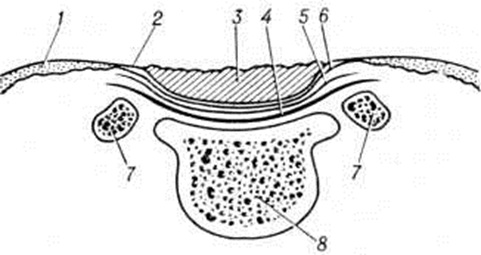

Спина бифидаСпина бифида (латынь spina шип, позвоночный столб + bifidus разделенный надвое, расщепленный) — порок развития позвоночника, характеризующийся незаращением позвонков и неполным закрытием позвоночного канала, часто сопровождающийся пороком развития спинного мозга. Спина бифида нередко сочетается с дисплазией внутренних органов и других отделов скелета. Спина бифида может наблюдаться в различных отделах позвоночника, однако чаще всего в пояснично-крестцовом отделе. Дефекты в позвоночнике могут сочетаться с грыжевыми выпячиваниями спинного мозга и его оболочек (смотри полный свод знаний: Спинной мозг, пороки развития). В 1641 год Тульпиус (N. Tulpius) впервые описал больного с опухолью на спине на месте незаращения позвонков и назвал это заболевание «spina bifida». Расщепление позвоночника без грыжевого выпячивания в 1875 год описал Р. Вирхов. Эта патология названа им скрытой позвоночной расщелиной (spina bifida occulta). Было установлено, что расщепленными могут быть дуги позвонков (spina bifida posterior) либо тела позвонков (spina bifida anterior). Этиология и патогенез Спина бифида окончательно не выяснены. Существует мнение, что в возникновении этой патологии играют роль инфекция, травма, интоксикация в период внутриутробной жизни плода. К факторам риска относят возраст матери, особенно после 30 лет, гинекологическое заболевания, применение противозачаточных средств, злоупотребление алкоголем в первые месяцы беременности. Предполагают, что в основе этого порока развития лежат наследственные факторы. В отношении механизма развития Спина бифида существуют две точки зрения. Одни исследователи считают первичным порок развития нервной трубки и гидроцефалию; другие полагают, что вначале появляется порок развития мезобласта либо позвоночника на более поздних этапах развития зародыша, а формирование порока развития спинного мозга происходит вторично. Классификации Спина бифида основаны на результатах патологоанатомических исследований. Наиболее полная и подробная классификация дана Ф. Реклингхаузепом. В настоящий, время в зависимости от степени недоразвития позвоночника, спинного мозга, его оболочек, покровных тканей различают следующие анатомические формы этого порока развития: рахисхизис (полный или частичный), спинномозговые грыжи, spina bifida complicata, spina bifida occulta, spina bifida anterior. Основным морфологический признаком рахисхизиса является незаращение мягких тканей, позвоночника, мозговых оболочек и спинного мозга (рисунок 1). Не сомкнувшийся в трубку спинной мозг лежит обнаженным; он представляет собой красноватую бархатистую плоскую массу, состоящую из большого количества расширенных сосудов и элементов мозговой ткани. При полном рахисхизисе описанная картина наблюдается на протяжении всего позвоночника, частичный рахисхизис обычно локализуется в поясничном отделе позвоночника. На месте дефекта дуг позвонков располагается не закрывшаяся в трубку зародышевая нервная пластинка — сосудисто-мозговая область (area medullovasculosa), которая лежит на мягкой оболочке спинного мозга. Участок последней от её края до края кожи, покрытый тонким слоем эпидермиса, был назван эпителиосерозной зоной (zona epithelioserosa). Кнаружи от этой зоны располагается кожа — кожная зона (zona dermatica). Если в субарахноидальном (подпаутинном) пространстве скапливается цереброспинальная жидкость, может возникнуть спинномозговая грыжа — миеломенингоцеле. Рахисхизис может сочетаться с расщеплением тел позвонков. При рахисхизисе, особенно полном, часто встречаются пороки развития головного мозга и других органов. Спинномозговые грыжи представляют собой грыжевидные выпячивания мозговых оболочек, нервных корешков или спинного мозга через щель позвоночника. В зависимости от состава грыжевого выпячивания и расположения цереброспинальной жидкости (между оболочками спинного мозга или в центральном канале) различают несколько форм спинномозговых грыж: Менингоцеле, менингорадикулоцеле, миеломенингоцеле, миелоцистоцеле (смотри полный свод знаний: Спинной мозг, пороки развития). Spina bifida complicata — незаращение дуг позвонков, сочетающееся с разрастаниями жировой и фиброзной ткани, а также опухолью типа липомы, фибромы и другие Последние располагаются под кожей, выполняют дефект в дугах позвонков, могут прорастать мозговые оболочки и срастаться с корешками спинномозговых нервов и спинным мозгом. |